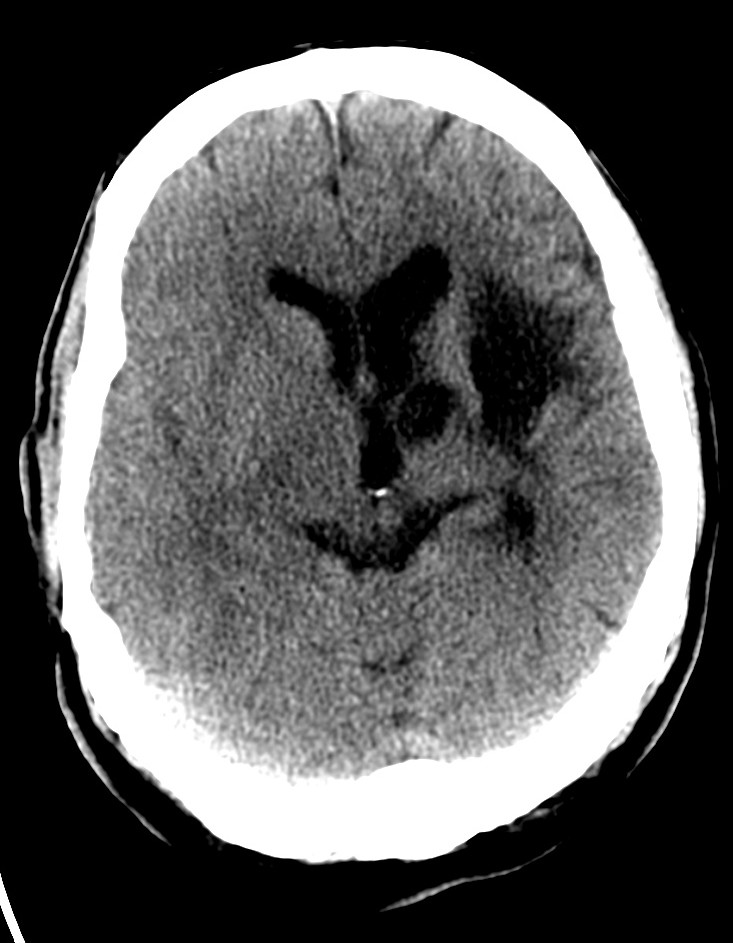

CASO 1:

Paciente con disminución de la conciencia y alteraciones de habla. El cuadro parece progresivo. Dislipemia y Diabetes Mellitus tipo II como antecedentes personales.

ASPECTS: Afectación Ribete Insular + Lenticular + Territorio M2 = 10 – 3 = 7 puntos.